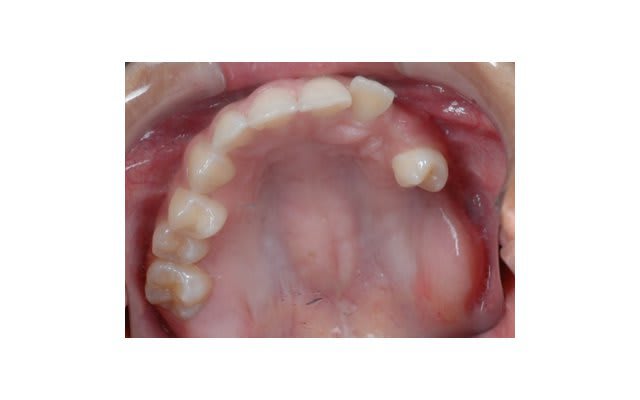

SI joint les photo intra buccal pre traitement et pendant traitement.

Comment expliquer vous le développement ce canting en frontal et de l'open bite en Postérieur ?

Je ne veux être une mauvaise LANGUE , mais pourquoi la prémolaire a été sacrifiée ???

Quel âge? Pourquoi autant de dents absentes? Y-a-il un syndrome associé ? Une ou plusieurs chirurgies precedentes pour des kystes? Des dents ankylosées?

Pas de dents postérieures de support et la mandibule flotte dans la face ?

La question de base, pourquoi manque-t-il le secteur 2 ? La prémolaire a été extraite comment et pourquoi ? Une pano serait bien quand même....

Photo 1 on met des brackets et fils un ans plus tard Photo 2

Il y avait ankylose de la 22 mais pas des molaires.

- Qu'il n'y avait aucun dent dans le secteur postérieur pour limiter les effet.